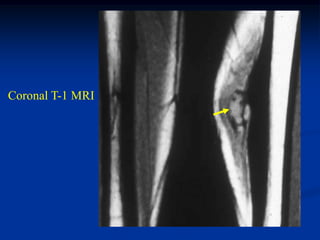

Case #1186

51 year male with

intramuscular lipoma

posterior compartment

thigh

Axial T-1 MRI